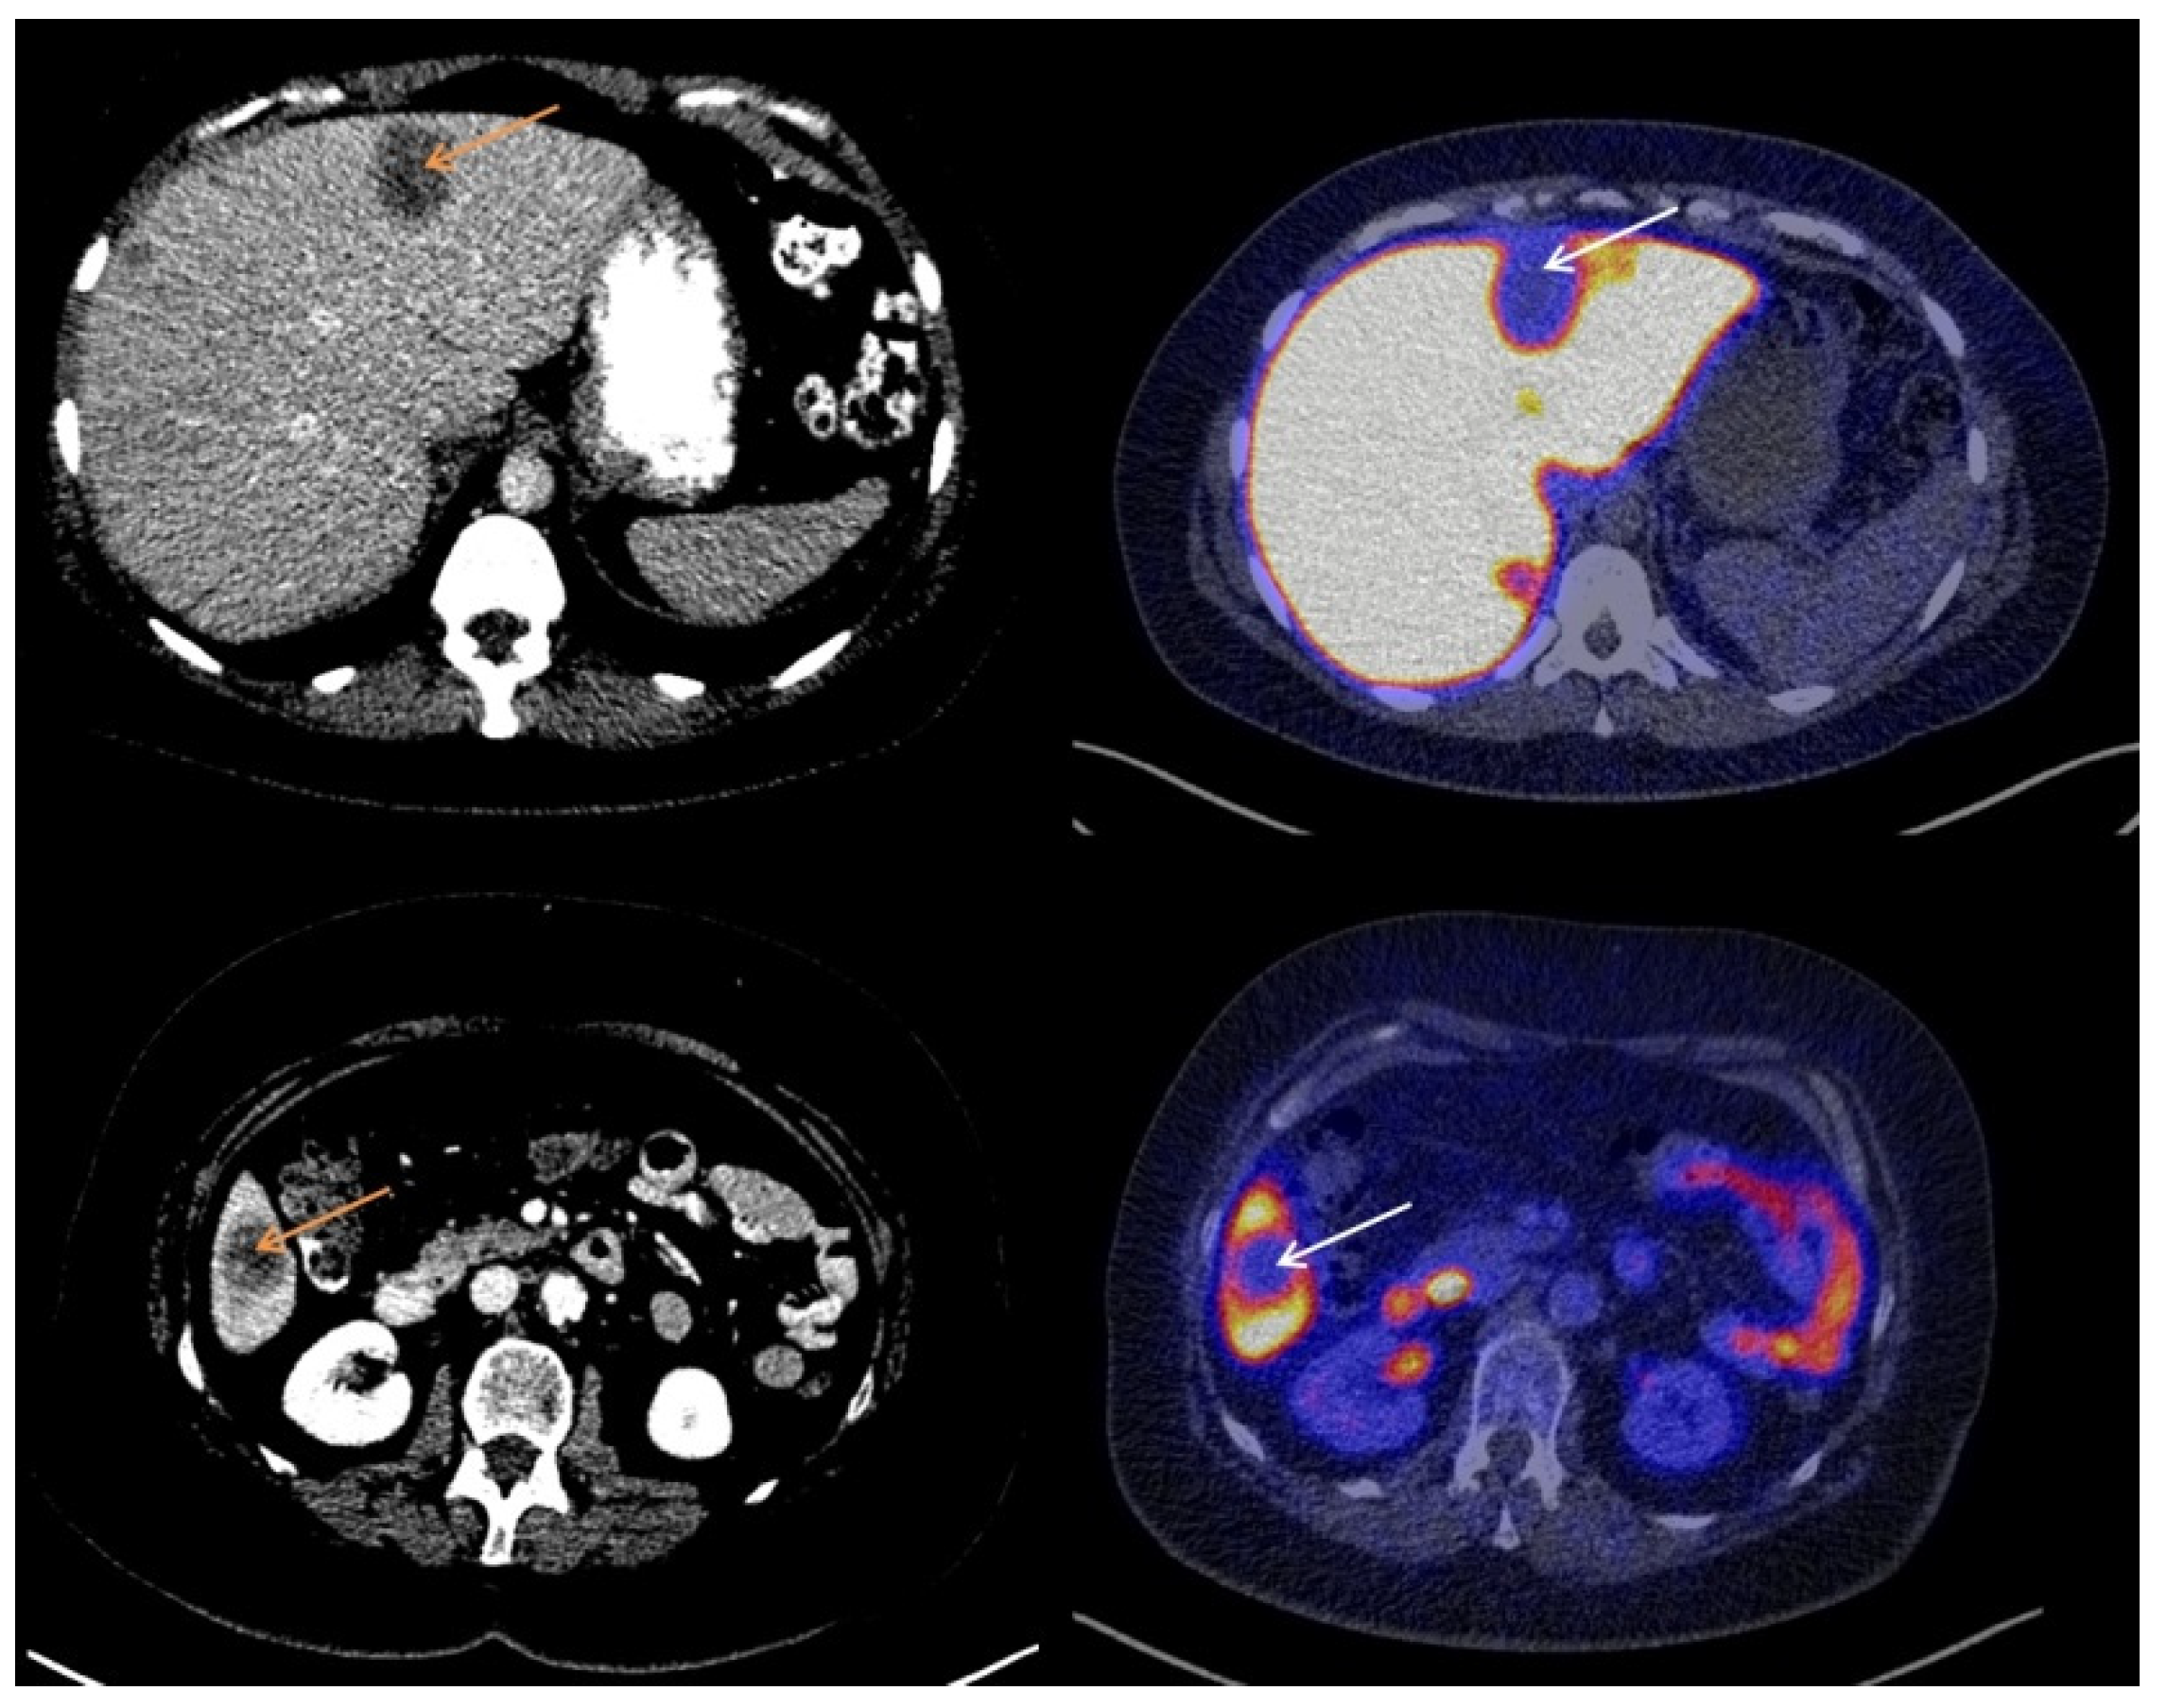

3.2. Visual Assessment of [18F]-FES Uptake

3.3. Quantitative Evaluation of [18F]-FES Uptake